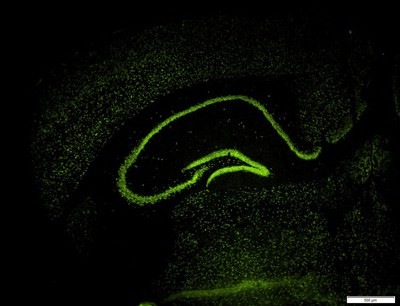

Visualisierung des räumlichen Expressionsmusters einer speziell im Gehirn angereicherten MicroRNA im Hippocampus der Maus mittels FISH (Fluoreszenz-in-situ-Hybridisierung). (Foto: Nicolas Singewald)

Die gezielte Beeinflussung von Genaktivierungen und zellulären Signalwegen bietet einen neuen Ansatz in der Therapie von Angstzuständen. Das zeigen aktuelle Ergebnisse eines vom Wissenschaftsfonds FWF geförderten Projekts von Innsbrucker Pharmazeuten. ,,Auslöschung" (extinction) ist eine klassische Methode der Angsttherapie: Erinnerungen an negative - angsterzeugende - Erfahrungen werden dabei durch wiederholte positive Erlebnisse, also durch neues Lernen, quasi überschrieben. Wer von einem Hund gebissen wurde, hat Angst vor Hunden. Wer danach aber viele problemlose Begegnungen mit Hunden hat, kann so die Angst besiegen. So einfach das klingt, und so effizient es auch helfen kann - nicht für jede Person klappt das gleich gut. Warum das so ist und was man dagegen tun kann, interessierte den Pharmazeuten Nicolas Singewald von der Universität Innsbruck in dem FWF-Projekt ,,Epigenetische Mechanismen gestörter Gedächtnisregulation" des Spezialforschungsbereichs ,,Cell signaling in chronic CNS disorders". Acetyl gegen Angst.